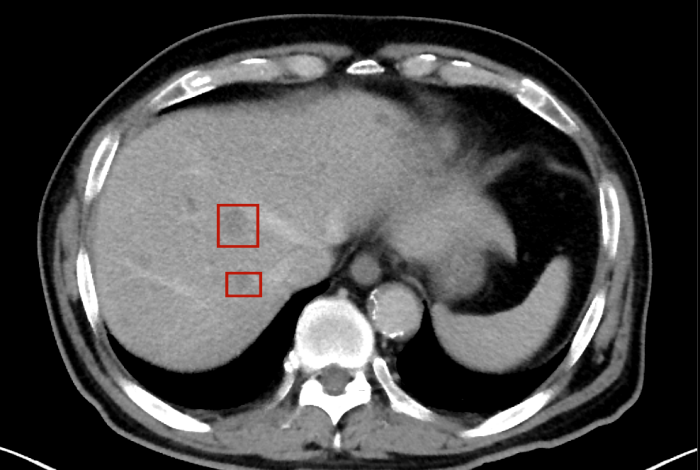

術(shù)后,萬秀萍為黃先生做進(jìn)一步的檢查,腹部磁共振(MRI)檢查顯示:肝臟區(qū)域出現(xiàn)了轉(zhuǎn)移病灶的陰影。

轉(zhuǎn)移病灶的陰影

目前,黃先生的腫瘤活動(dòng)已得到有效抑制,肝臟轉(zhuǎn)移灶未見爆發(fā)性進(jìn)展,病情整體保持穩(wěn)定。